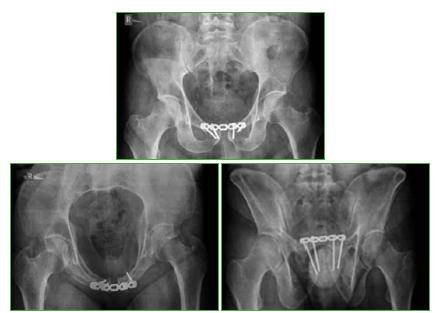

Flegmasia cerúlea dolens posquirúrgica inmediata en el tratamiento de una fractura de pelvis. Reporte de Caso

La flegmasia cerúlea dolens es una presentación poco habitual y grave de una trombosis venosa profunda producida por una obstrucción al flujo venoso de salida de la extremidad inferior, que conlleva un alto grado de morbilidad. Este cuadro no ha sido comunicado como complicación del tratamiento definitivo de una fractura de pelvis. Consideramos que una breve descripción del tema y la presentación de un caso pueden ser útiles para el cirujano ortopédico ante una situación similar.Descargas